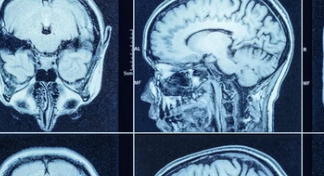

- 뇌 MRI:

- 신경계 이상 여부를 정밀하게 진단.